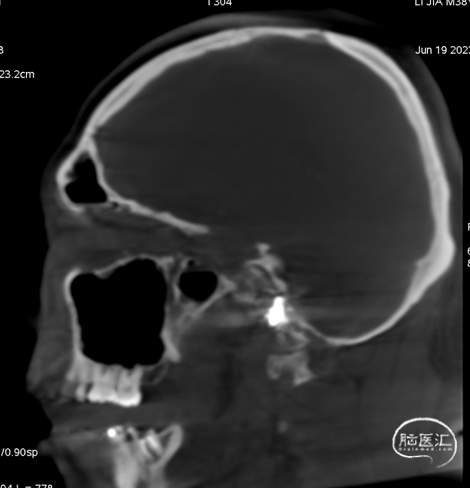

术前CT见左侧眼上静脉扩张

术后铸胶形态及CT下铸胶位置,可见瘘口位于左侧舌下神经管区域。